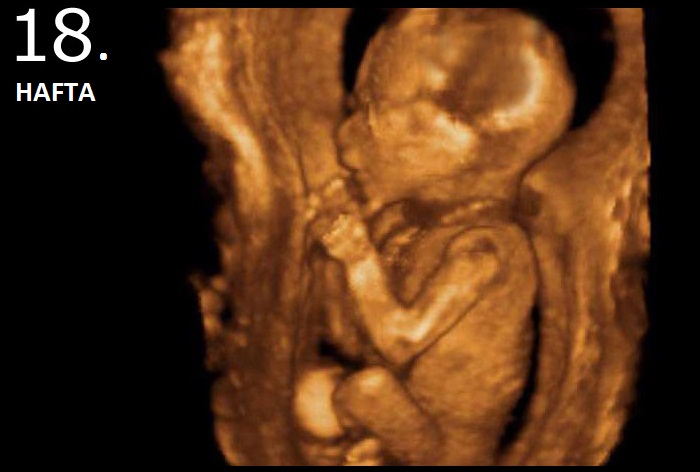

16 – 18 haftalık fetus

Anne karnında 18 haftalık bebeğin görünümü.jpg